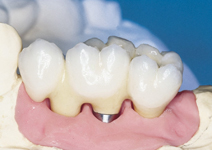

Klasickým příkladem a indikací pro použití implantátu je ztráta jednoho zubu (v tomto případě v předním – frontálním úseku) v jinak zdravém, nepoškozeném chrupu.

Nejčastější příčinou takové ztráty je sportovní nebo dopravní úraz.

Náhrada jednoho zubu pomocí implantátu je možná také v postranním úseku chrupu. Při ztrátě většího počtu zubů ve frontálním nebo postranním úseku může být mezer uzavřena větším počtem jednotlivých implantátů.

Při ošetření pomocí jednotlivých implantátů zůstávají sousední zuby neporušené – intaktní. Při klasickém ošetření pomocí můstků musejí být tyto zuby obroušeny!